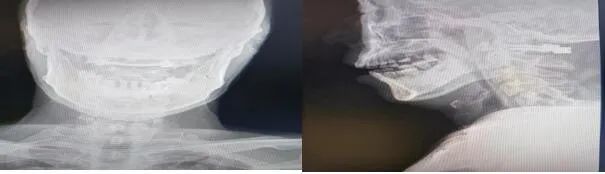

骨一科医生对患者经过全面的术前检查后,严密制定手术方案。由程福宏主任主刀,葛大明副主任医师配合,顺利完成了寰椎骨折切开复位椎弓根钉棒固定术,手术最大可能的减少了固定节段,最大程度的保留了颈椎的活动度,术后患者四肢肌力较术前明显恢复。目前患者已顺利出院,生活可自理。